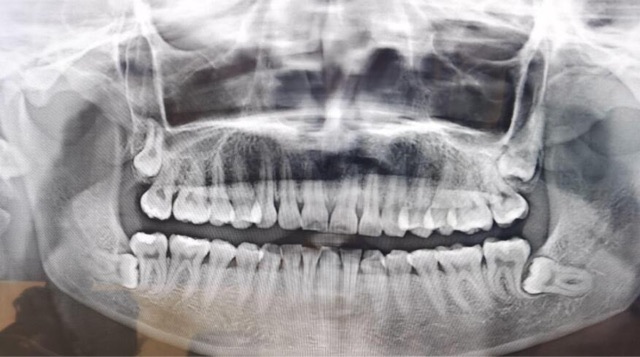

智齿,也称为第三磨牙,是人类的额外一对臼齿,通常在16岁至25岁之间开始出现。它们是人类进化的痕迹,起源于远古时期我们祖先的食物选择的变化。然而,由于智齿的生长常伴随着问题和不适,许多人需要通过拔牙来解决这些问题。智齿的问题主要源于其冠部的生长问题。由于人类的口腔逐渐缩小,智齿往往没有足够的空间来正常生长和发育。

智齿可能不在正确的位置上,可能向前倾斜、向后倾斜或垂直倒置。这些错位可能对邻近的牙齿造成压力和移位,导致不适和疼痛。

智齿可能仅部分冒出牙龈表面,造成牙龈肿胀和不适。为了解决这些问题,许多人选择拔除智齿。【足记网】根据情况的严重程度,医生会决定是否需要拔除智齿。拔除智齿通常是在局部麻醉下进行,医生会在口腔内提供适当的舒适度。